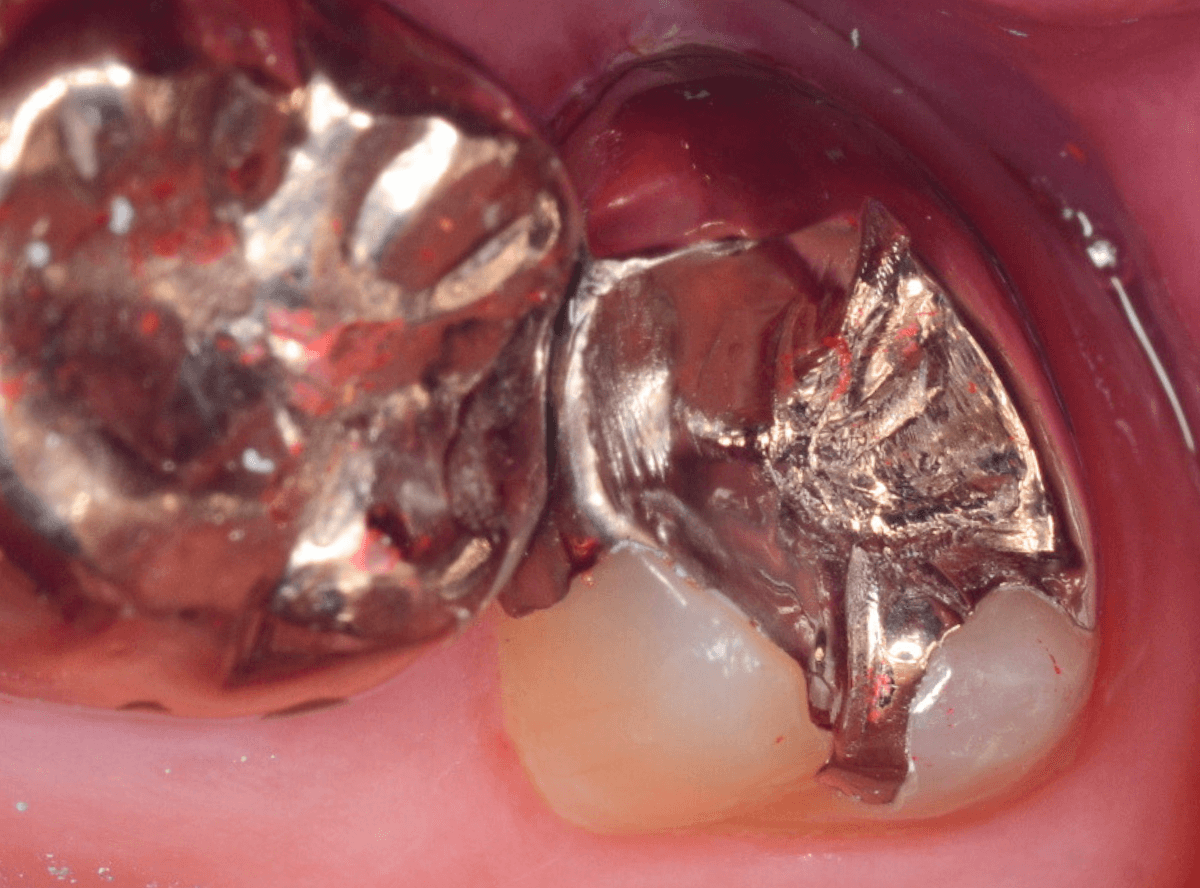

Case.7 治療を中断して、神経に達するほど虫歯が進行した

こちらは正確には「気づかない」ではなく、症状がないため治療途中の虫歯を放置してしまった方の例です。

つめていたセメントが剥がれ、大きな穴が空いています。

レントゲン写真で確認します。

青い部分が神経、赤い部分が虫歯です。

虫歯を放置してしまったため、歯の神経まで虫歯が達しています。

また、手前の歯の歯肉の中まで、虫歯は大きく進行しています。

慎重に虫歯を除去します。

手前の歯は神経の処置をしているため、どれだけ虫歯が進行しても症状はなく、歯肉を除去しながら深い虫歯の処置をしています。

ここまで虫歯を除去しても、染色液で染めだすと赤く染まってきます。

神経に触ってしまわないがとても怖いですが、取り残してしまうと治療の意味がなくなってしまいますので、より慎重に虫歯を除去します。

奥歯の虫歯をなんとか全て除去できましたが、神経が一部顔を覗かせている状況です。

こうなると、治療後に痛みが出て、神経を除去しなければいけない可能性があります。

神経を保護するお薬をつめて、セメントで蓋をします。

あとは、手前の虫歯の治療をしながら、痛みが出ない事を祈るばかりです。

絶対に治療を中断しないよう、念を押したのは言うまでもありません。。。